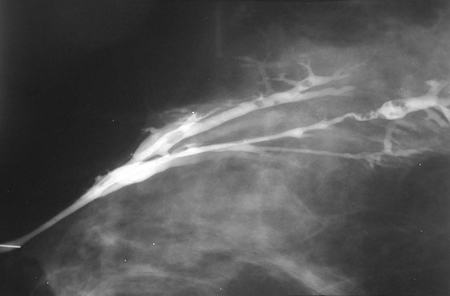

Papiloma de mama

Una galactorrea sanguinolenta constituye una característica habitual del papiloma mamario. En ocasiones, esta clase de lesión puede detectarse como una masa dentro de la mama. Las proliferaciones se producen a menudo dentro de los conductos mamarios (papilomas intraductales). Estas lesiones suelen ser benignas, aunque pueden estar relacionadas con hallazgos histológicos de atipia celular, carcinoma ductal in situ (CDIS) tipo papilar o cáncer papilar invasivo.[Figure caption and citation for the preceding image starts]: Ductograma en el que se observan múltiples papilomas intraductalesCortesía de la Dra. Nancy Pile, University of Louisville; utilizada con autorización [Citation ends].